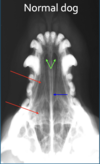

What is shown in this image?

A